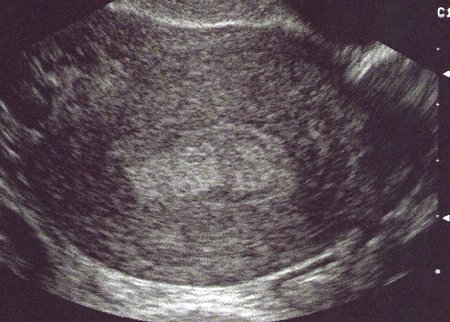

Polype muqueux, hyperéchogène. Coupe transversale (Cliché : Dr. C. TALMANT)